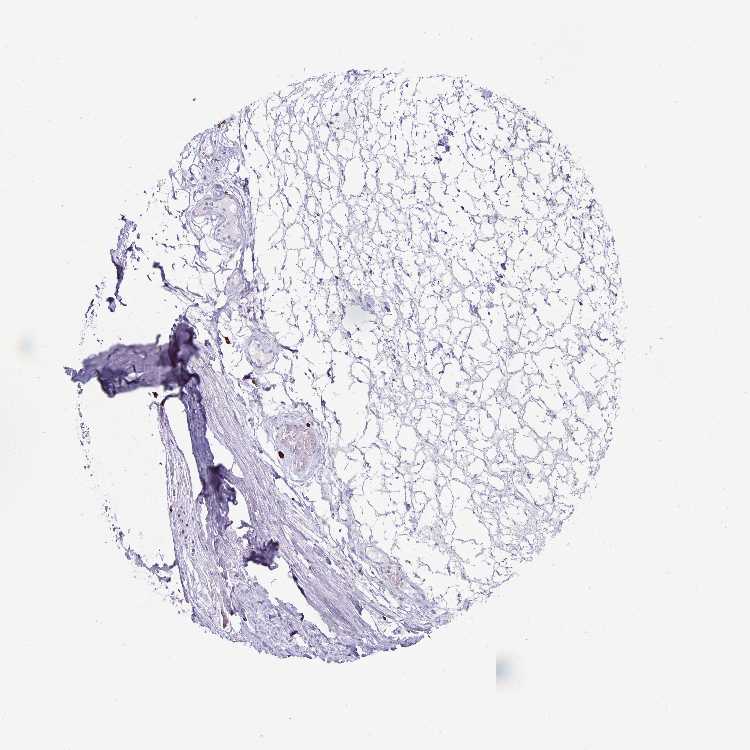

SOFT TISSUE 1 - Antibody stainingi

Antibody staining in the annotated cell types in the current human tissue is reported as not detected, low, medium, or high, based on conventional immunohistochemistry profiling in selected tissues. This score is based on the combination of the staining intensity and fraction of stained cells.

Each image is clickable and will lead to virtual microscopy that enables deeper exploration of all samples and also displays staining intensity scores, fraction scores and subcellular localization as well as patient and tissue information for each sample.

Antibody HPA063181Antibody HPA065895

Chondrocytes Not detected-

Fibroblasts Not detectedNot detected

SOFT TISSUE 2 - Antibody stainingi

Peripheral nerve Not detectedNot detected